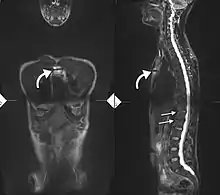

X-rays

The earliest changes demonstrable by plain x–ray shows erosions and sclerosis in sacroiliac joints. Progression of the erosions leads to widening of the joint space and bony sclerosis. X-ray spine can reveal squaring of vertebrae with bony spur formation called syndesmophyte. This causes the bamboo spine appearance. A drawback of X-ray diagnosis is the signs and symptoms of AS have usually been established as long as 7–10 years prior to X-ray-evident changes occurring on a plain film X-ray, which means a delay of as long as 10 years before adequate therapies can be introduced.[25]

Options for earlier diagnosis are tomography and MRI of the sacroiliac joints, but the reliability of these tests is still unclear.

Lateral X-ray of the mid back in ankylosing spondylitis

Lateral X-ray of the neck in ankylosing spondylitis

X-ray showing bamboo spine in a person with ankylosing spondylitis